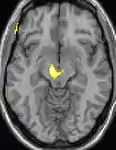

Positron emission tomography (PET) scans indicate the brain areas which are activated during attack only, compared to pain free periods. These pictures show brain areas that are active during pain in yellow/orange color (called "pain matrix"). The area in the center (in all three views) is specifically activated during CH only. The bottom row voxel-based morphometry (VBM) shows structural brain differences between individuals with and without CH; only a portion of the hypothalamus is different.[36]